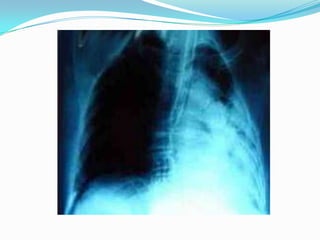

EXAMENESBroncoscopia Radiografía de tórax: Detecta los siguientes signos radiológicos:Desplazamiento de las cisuras.Desplazamiento de mediastinoElevación del hemidiafragma.Aproximación arcos costales.Enfisema compensador.Aumento de la densidad pulmonar sin broncograma.En el adulto previamente sano que presente una atelectasia hay que sospechar una neoplasias que obstruye el bronquio.

EXAMENESBroncoscopia Radiografía detórax: Detecta los siguientes signos radiológicos:Desplazamiento de las cisuras.Desplazamiento de mediastinoElevación del hemidiafragma.Aproximación arcos costales.Enfisema compensador.Aumento de la densidad pulmonar sin broncograma.En el adulto previamente sano que presente una atelectasia hay que sospechar una neoplasias que obstruye el bronquio.